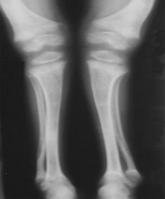

本病的發生髮展是一個連續過程。依據年齡、病史、症狀、體徵、X線及血生化等項綜合資料可分為活動期(初期、激期)、恢復期和後遺症。無條件作X線及血生化檢查者,可只根據臨床資料進行分析。 1、初期:多自3個月左右開始發病。早期常有非特異的神經精神症狀如夜驚、多汗、煩躁不安等。枕禿也較常見。同時可有輕度的骨骼改變體徵。X線片可無異常或見臨時鈣化帶模糊變薄、乾骺端稍增寬。血生化改變輕微,血鈣、血磷正常或稍低,鹼性磷酸酶正常或稍高。 2、激期:常見於3個月至2歲的小兒。有明顯的夜驚、多汗、煩躁不安等症狀。同時可有中度的骨骺改變體徵。X線片可見臨時鈣化帶模糊消失,乾骺端增寬,邊緣不整呈雲絮狀,毛刷狀或杯口狀,骨骺軟骨加寬。血鈣、血磷均降低,鹼性磷酸酶增高。 3、恢復期:活動期經曬太陽或維生素D治療後,症狀消失,體徵逐漸減輕、恢復。X線片可見臨時鈣化帶重現、增寬、密度加厚。血鈣、血磷、鹼性磷酸酶恢復正常。 4、後遺症:多見於3歲以後的小兒。經治療或自然恢復,症狀消失,骨骼改變不再進展。X線及血生化檢查正常,僅留有不同程度的骨骼畸形。 治癒標準:症狀已消失1-3個月,體徵減輕或恢復正常,觀察3-6個月無變化。輕、中度者一般不留後遺症。重度者可留有不同程度的骨骼畸形。X線及血生化檢查正常,或僅表現有臨時鈣化帶增寬、密度加厚。